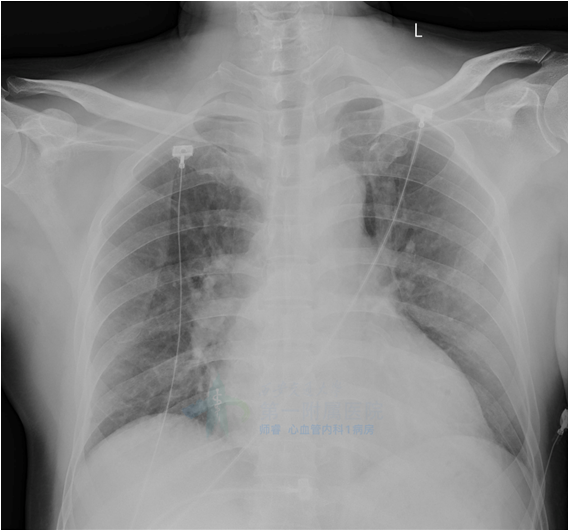

两肺纹理增重

心影增大